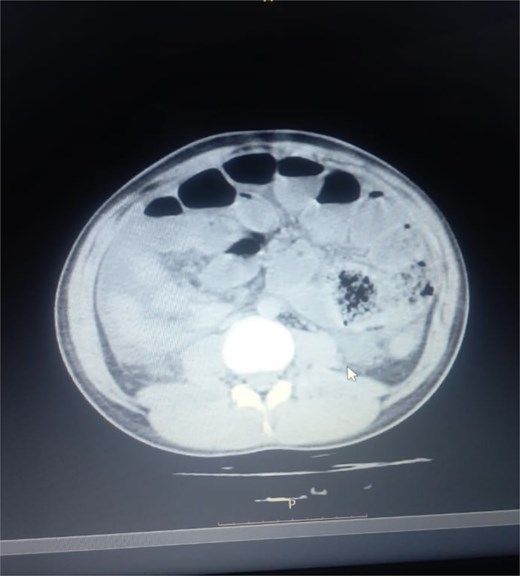

Initial radiographic evaluation with a plain abdominal X-ray confirmed the clinical suspicion of acute intestinal obstruction, demonstrating multiple air-fluid levels and diffuse small bowel dilatation (Fig. 1). To further delineate the underlying etiology, a contrast-enhanced computed tomography (CECT) scan was performed; providing critical diagnostic information it revealed, in the right iliac fossa, a striking encapsulation of the small intestine loops within a sac-like membrane, accompanied by ascites. This constellation of findings formed a pathognomonic cocoon-like structure (Fig. 2). Furthermore, the CECT identified a concurrent gut malrotation, evidenced by a left-sided displacement of the colon (Fig. 3). Laboratory findings showed an elevated total leukocyte count (TLC) of 21 000, indicative of inflammation, while other parameters were within normal limits. The patient underwent an exploratory laparotomy. Intraoperatively, the abdominal viscera were encased within a thick fibrous membrane (Fig. 4), containing ascitic fluid. The membrane was incised, adhesiolysis was performed, and the entrapped small bowel loops were released, and then a kink in the small intestine causing obstruction was identified and corrected. Additionally, the appendix was found to be secondarily involved in the encapsulating process. It was encased in the dense fibrocollagenous membrane, forming an inflammatory mass consistent with chronic serositis and localized fibrosis, rather than a classic acute appendicular phlegmon. Based on this intraoperative assessment that the mass was a manifestation of the cocoon’s chronic inflammation, a simple appendectomy was performed instead of a more extensive right hemicolectomy. This procedure was necessary to achieve complete release of the entrapped bowel, remove this localized inflammatory focus, and obtain a specimen for histopathology to definitively rule out a primary appendiceal pathology as a secondary cause of the peritonitis. Furthermore, ascitic fluid analysis showed no bacterial or mycobacterial growth, ruling out tuberculosis and the histopathological examination confirmed the fibrocollagenous nature of the membrane. The patient recovered well postoperatively and was discharged on the sixth day with advice for a follow-up after 2 weeks. At the follow-up visit, he reported no symptoms, and abdominal imaging confirmed the absence of obstruction. Histology further confirmed the benign fibrous nature of the membrane, with no signs of malignancy.

Intraoperative findings of idiopathic Sclerosing encapsulating peritonitis. The image displays the abdominal viscera entirely encased within a smooth, thick, cocoon-like sac, consistent with abdominal cocoon syndrome. The whitish, glistening appearance of the membrane is characteristic of its dense, fibrocollagenous composition, which was later confirmed by histopathology.